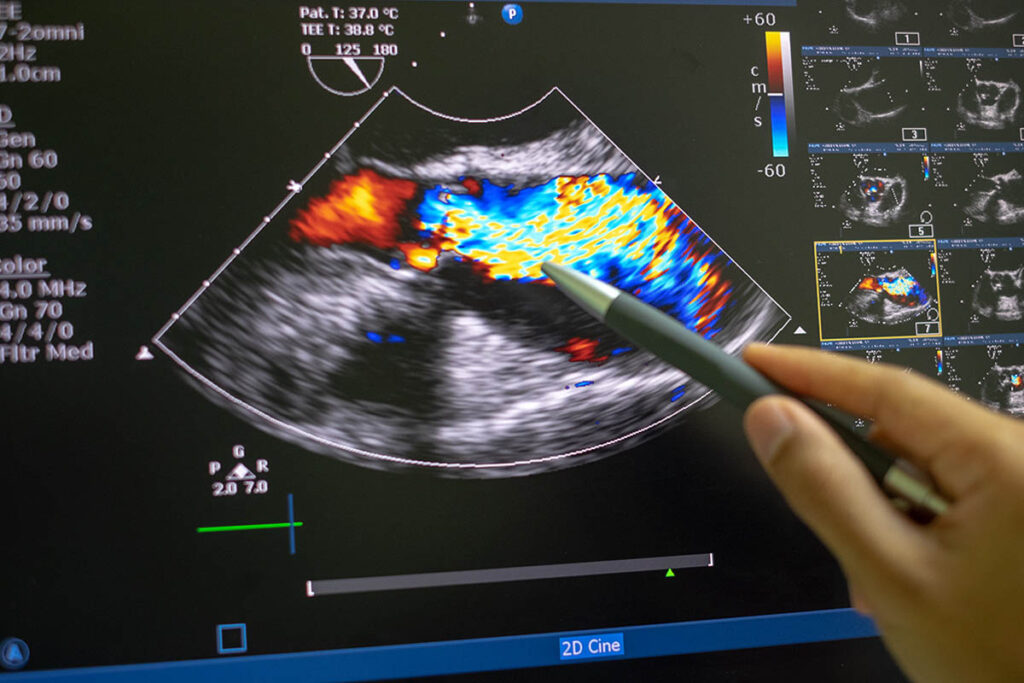

诊断性心脏超声检查,也称为超声心动图检查,使用高频声波对患者进行心脏诊断。作为患者护理团队的一部分,心脏超声诊断医师评估患者并向心脏病专家提供信息以进行诊断和患者健康监测。

探索人类心脏的解剖学、生理学和疾病,同时使用超声波物理学的基础知识来操作最先进的超声波系统。

培养扫描技能,以安全地完成心脏检查,为评估真实患者做好准备。拓宽对心脏病理学的理解。